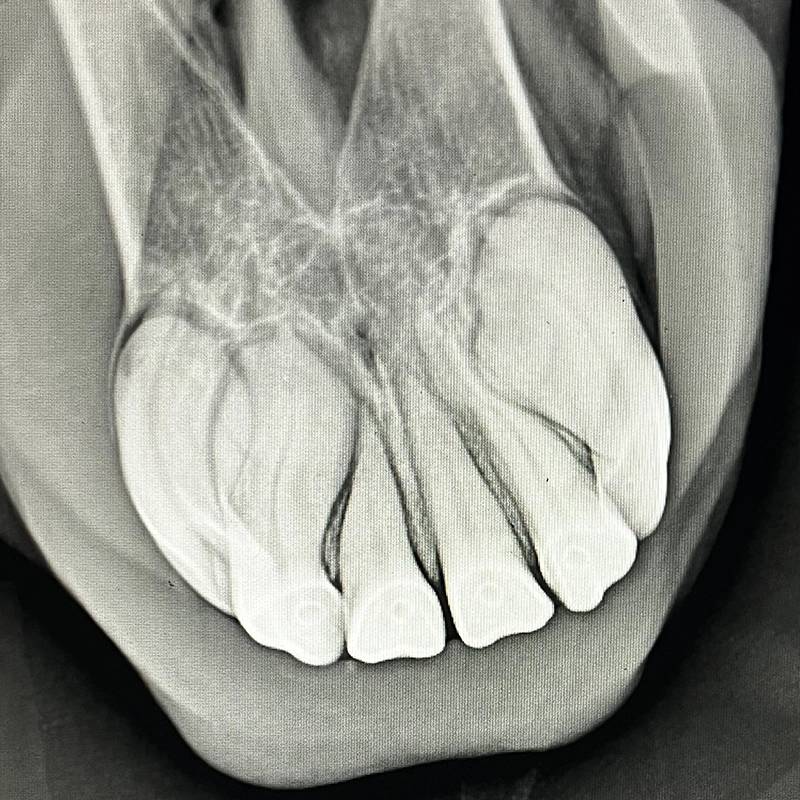

EOTRH, Equine Odontoclastic Tooth Resorption and Hypercementosis, is a complex disease process affecting the incisors and surrounding tissues, typically developing over many years. Progressive destruction of dental and bony structures, along with structural changes, leads to inflammation and, in some cases, significant pain. Especially in early stages, this pain is not always clearly detectable.

If the incisors are significantly damaged and conservative treatments no longer provide sufficient relief, extraction of the affected teeth is often the last option to permanently eliminate chronic pain and restore the horse’s quality of life.